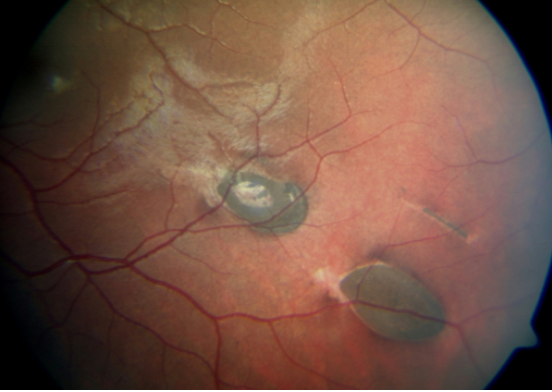

- Hipertrofia congênita do epitélio pigmentar da retina (CHRPE).